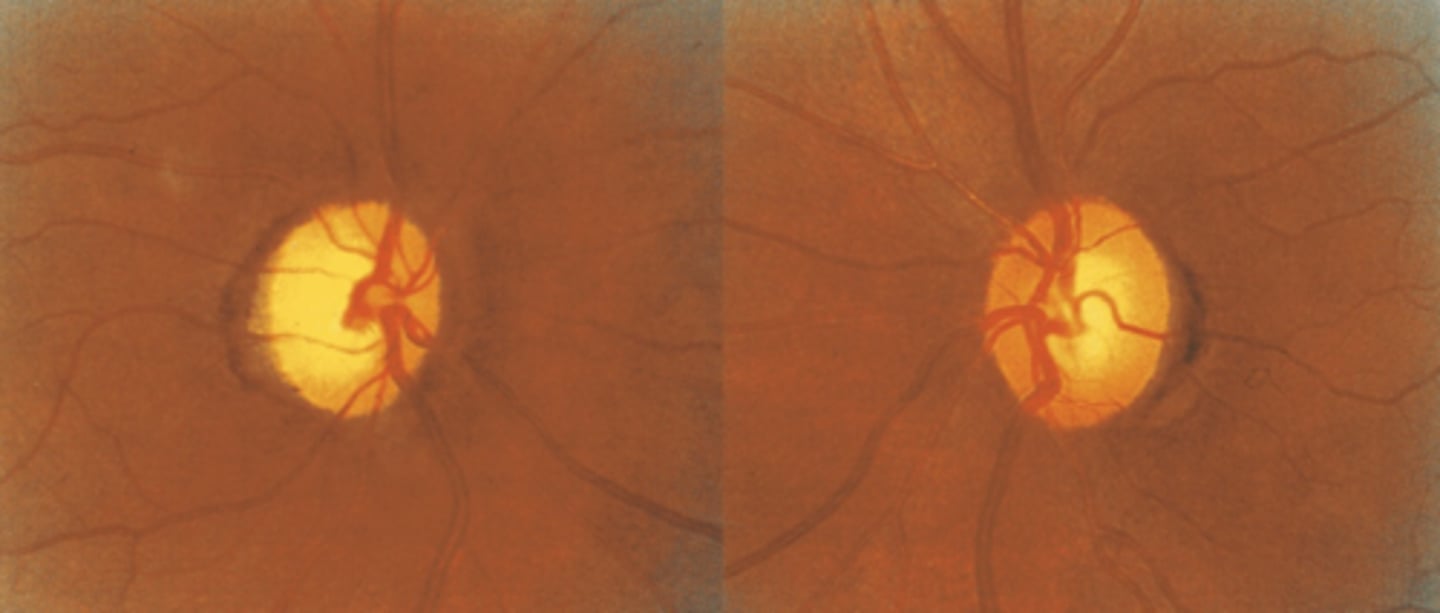

What cause of descending optic atrophy is seen here?

neoplasm in cranium (craniopharyngioma) causing compression